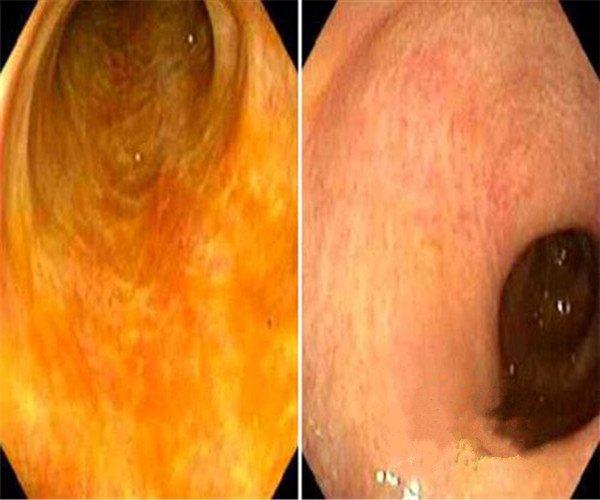

潰瘍性結腸炎圖片

輕微潰瘍性結腸炎前後對比